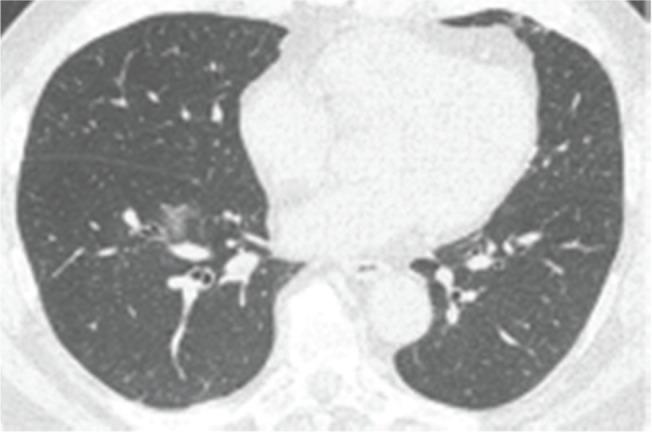

The coronavirus disease (COVID-19), caused by the severe acute respiratory syndrome coronavirus 2 (SARS-CoV-2), emerged in Wuhan city and was declared a pandemic in March 2020. Although the virus is not restricted to the lung parenchyma, the use of chest imaging in COVID-19 can be especially useful for patients with moderate to severe symptoms or comorbidities. This article aimed to demonstrate the chest imaging findings of COVID-19 on different modalities: chest radiography, computed tomography, and ultrasonography. In addition, it intended to review recommendations on imaging assessment of COVID-19 and to discuss the use of a structured chest computed tomography report. Chest radiography, despite being a low-cost and easily available method, has low sensitivity for screening patients. It can be useful in monitoring hospitalized patients, especially for the evaluation of complications such as pneumothorax and pleural effusion. Chest computed tomography, despite being highly sensitive, has a low specificity, and hence cannot replace the reference diagnostic test (reverse transcription polymerase chain reaction). To facilitate the confection and reduce the variability of radiological reports, some standardizations with structured reports have been proposed. Among the available classifications, it is possible to divide the radiological findings into typical, indeterminate, atypical, and negative findings. The structured report can also contain an estimate of the extent of lung involvement (e.g., more or less than 50% of the lung parenchyma). Pulmonary ultrasonography can also be an auxiliary method, especially for monitoring hospitalized patients in intensive care units, where transfer to a tomography scanner is difficult.